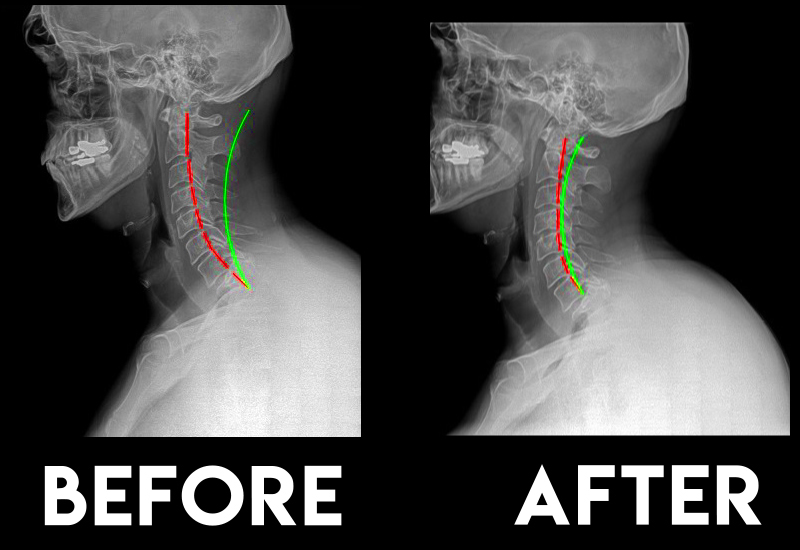

Neck pain

Better posture